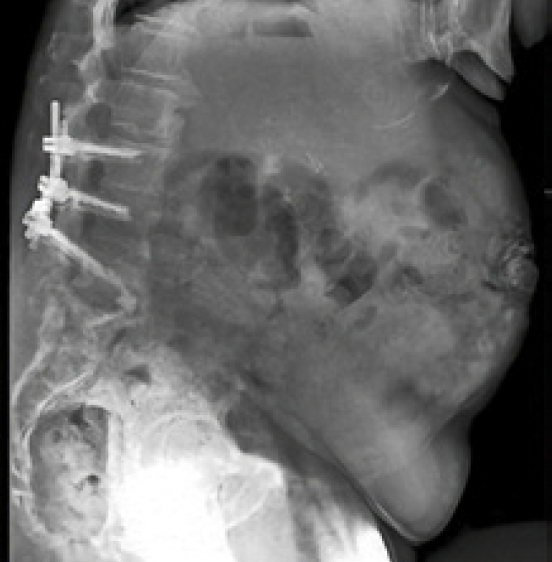

Surgical Treatment:

- T10-pelvis posterior fixation and fusion

- L4 pedicle subtraction osteotomy (PSO)

- Bilateral placement of iFuse 3DTM implants using the Bedrock® technique

- Four points of SIJ fixation

Post-op:

- PI-LL: 43° to 7°, C7-SVA: 24cm to 5cm

- Back and SI joint pain improved post-operatively. Improvement persisted at 2 years.2